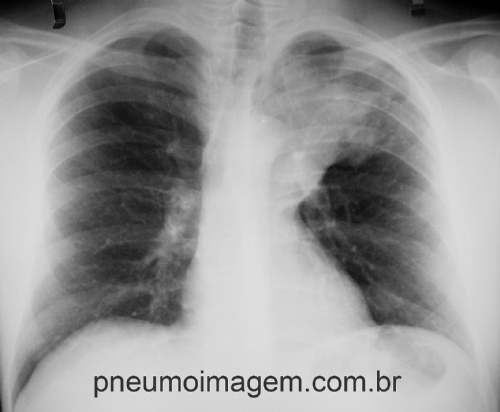

UM EM CADA 4 ADULTOS NÃO RESPONDE AO TRATAMENTO AMBULATORIAL DA PNEUMONIA

Aproximadamente um em cada quatro adultos tratados com monoterapia ambulatorialmente para pneumonia adquirida na comunidade (PAC) não respondeu ao tratamento, de acordo com um novo estudo de coorte retrospectivo.